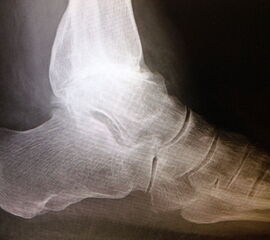

Anbohren der subchondralen Sklerosezone mit einem 2 bis 3,5 mm Bohrer zur Verbesserung der Durchblutung (Abb. 4).

Abbildung 4